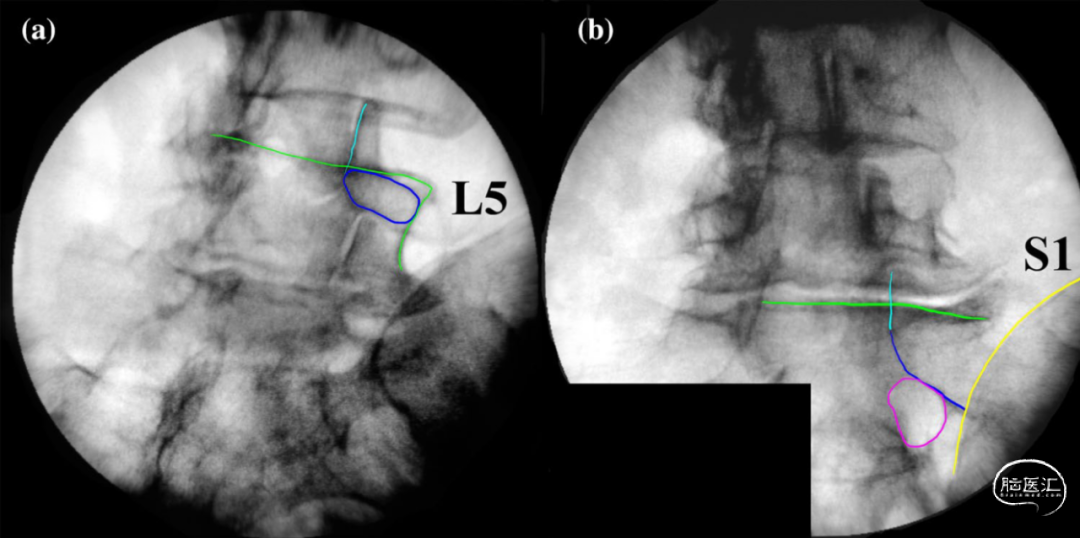

侧卧位透视下椎弓根螺钉放置可通过不同的C形臂位置或旋转手术床位置进行控制(图1、2)。

图1. 患者取侧卧位,在C形臂X线机透视下的隧道视图进行椎弓根定位。a. 从后方进行定位;b. 从前方进行定位。

图2. L5椎弓根(a)和S1椎弓根(b)隧道视图的透视标记。L5上终板(绿色)、上关节突(青色)和椎弓根(蓝色)以及S1孔(紫色)和髂嵴(黄色)。